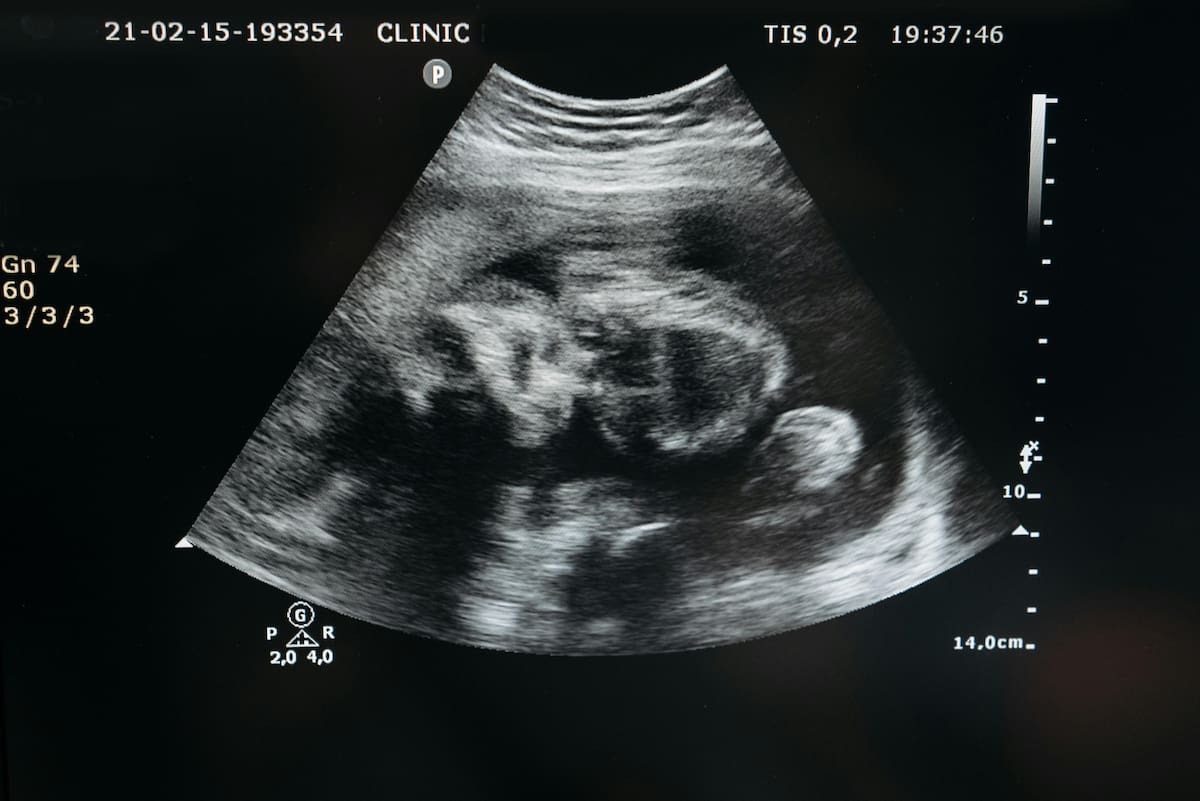

El motivo: se molestó al saber que su tercer hijo también sería una niña.

Los hechos ocurrieron el 4 de septiembre de 2024, cuando Garnier atacó brutalmente a su esposa, Samantha Garnier, de 29 años y con cinco meses de embarazo, y a sus hijas Izzie, de 6 años, y Adelina, de 9.

Samantha Garnier tenía previsto dar a luz en febrero de este año. Su padre también informó que ha adoptado legalmente a sus nietas, quienes aún están en recuperación de sus heridas.